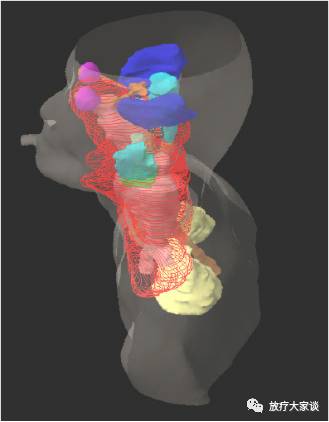

4.6 三维显示

4.6.1轮廓线

4.6.2表面/实体

4.6.3透明

放疗计划系统有哪些放射治疗计划系统(TPS)介绍_https://www.jmylbn.com_新闻资讯_第7张